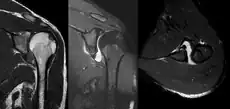

A diagnosis of shoulder dislocation is often suspected based on the person's history and physical examination. Radiographs are made to confirm the diagnosis. Most dislocations are apparent on radiographs showing incongruence of the glenohumeral joint. Posterior dislocations may be hard to detect on standard AP radiographs, but are more readily detected on other views. After reduction, radiographs are usually repeated to confirm successful reduction and to detect bone damage. After repeated shoulder dislocations, an MRI scan may be used to assess soft tissue damage. In regards to recurrent dislocations, the apprehension test (anterior instability) and sulcus sign (inferior instability) are useful methods for determining predisposition to future dislocation.

An anterior dislocation of the shoulder